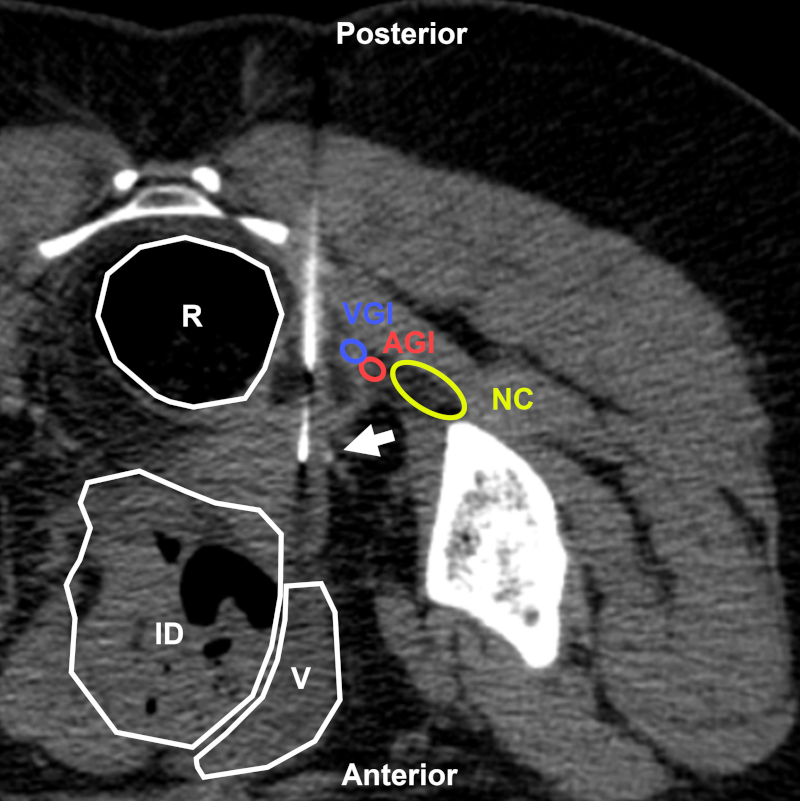

Mujer de 59 años con antecedentes de cáncer de mama en reestadificación por lesión lítica. BP con abordaje directo posterior (flecha) bajo TC. Estructuras a evitar: NC: nervio ciático; AGI: arteria glútea inferior; VGI: vena glútea inferior; NO: nervio obturador. Aguja utilizada: Franseen 18 G. Diagnóstico final: infiltración por adenocarcinoma de origen mamario.

En cuanto al abordaje posterior, la vía transglútea (también llamada transciática) permitirá realizar BP de lesiones ubicadas por detrás de la vejiga o en topografía perirrectal. El acceso puede ser posterior propiamente dicho (Fig. 20) o posterolateral (Fig. 21). Por vía posterior, la intervención deberá efectuarse lo más cerca posible del sacro a través del ligamento sacroespinoso. Una de las virtudes de este abordaje es que respeta el peritoneo. No obstante, al tener que realizarse en posición prono, puede resultar incómoda para algunos pacientes. Como alternativa, el posicionamiento puede ser en decúbito lateral1,29,31,32. Se deberá evitar lesionar los nervios sacros, el nervio ciático, los vasos glúteos e ilíacos, y el recto1,29.